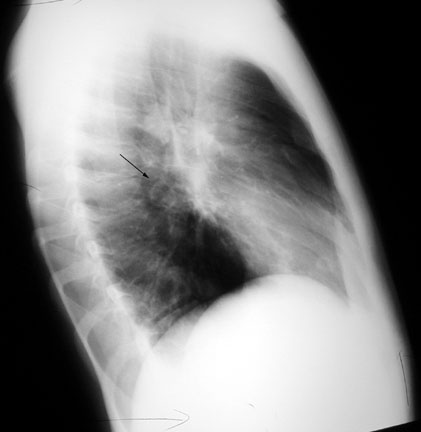

Case 37

Lateral

Labeled Image

How do you distinguish LL lung abscess from hiatal hernia?